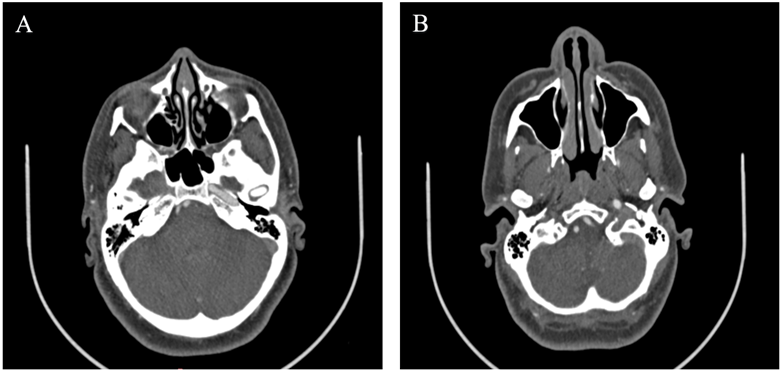

The CT scan with bone reconstruction showed the absence of the right carotid canal.

Figure 2: Axial CT scan of the base of the skull showing the absence of the right carotid canal (A). No opacification of the right internal carotid artery (B).